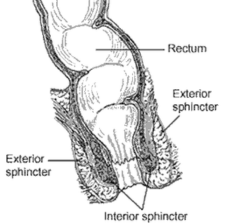

Sphincter Repair for Incontinence

This procedure repairs a damaged or weakened anal sphincter that occurred during childbirth. Doctors identify an injured area of muscle and free its edges from the surrounding tissue. They then bring the muscle edges back together and sew them in an overl